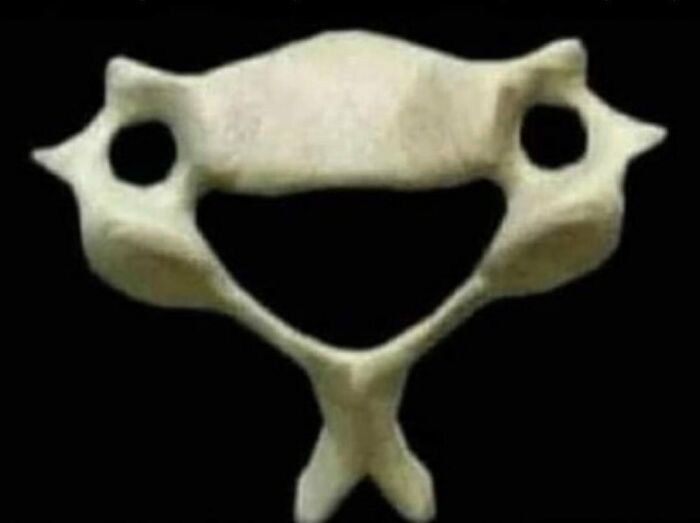

If you're feeling sad, remember this C6 vertebra and how happy it is to hold you (and your head) up every day